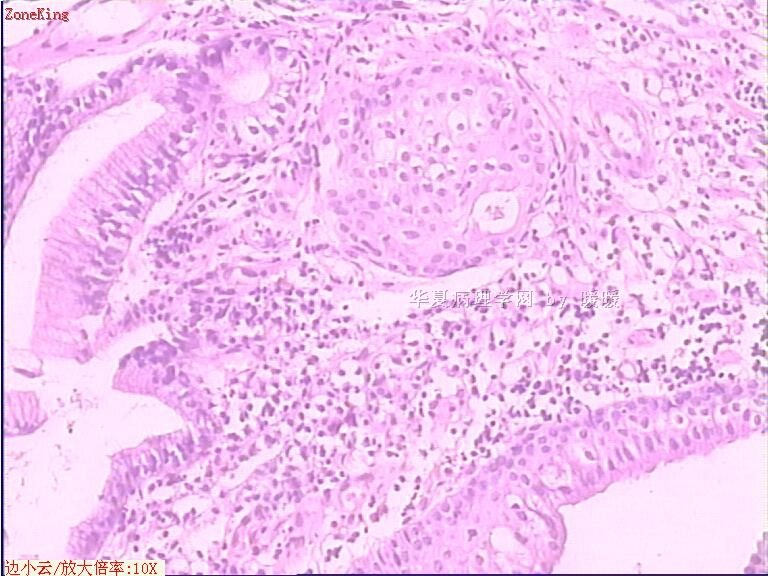

贲门息肉?

姓    名: ××× 性别:  女 年龄:  53

简要病史:  胃镜见,食道下段齿状线上可见一圆形隆起,有蒂,表面光滑,大小0.5X0.5X0.3cm.

各位老师,胃粘膜处出现的鳞状上皮有问题么?

• 贲门息肉?图2

图2

正好是齿状线腺鳞交界处粘膜

鳞状上皮没大问题,可能受炎症影响,稍有增生.

可能是炎症刺激下上皮鳞状化生

本帖最后由 于 2009-11-21 09:51:00 编辑   谢谢各位老师指点,最终诊断为:贲门慢性炎症,伴局灶细胞轻度异型增生。